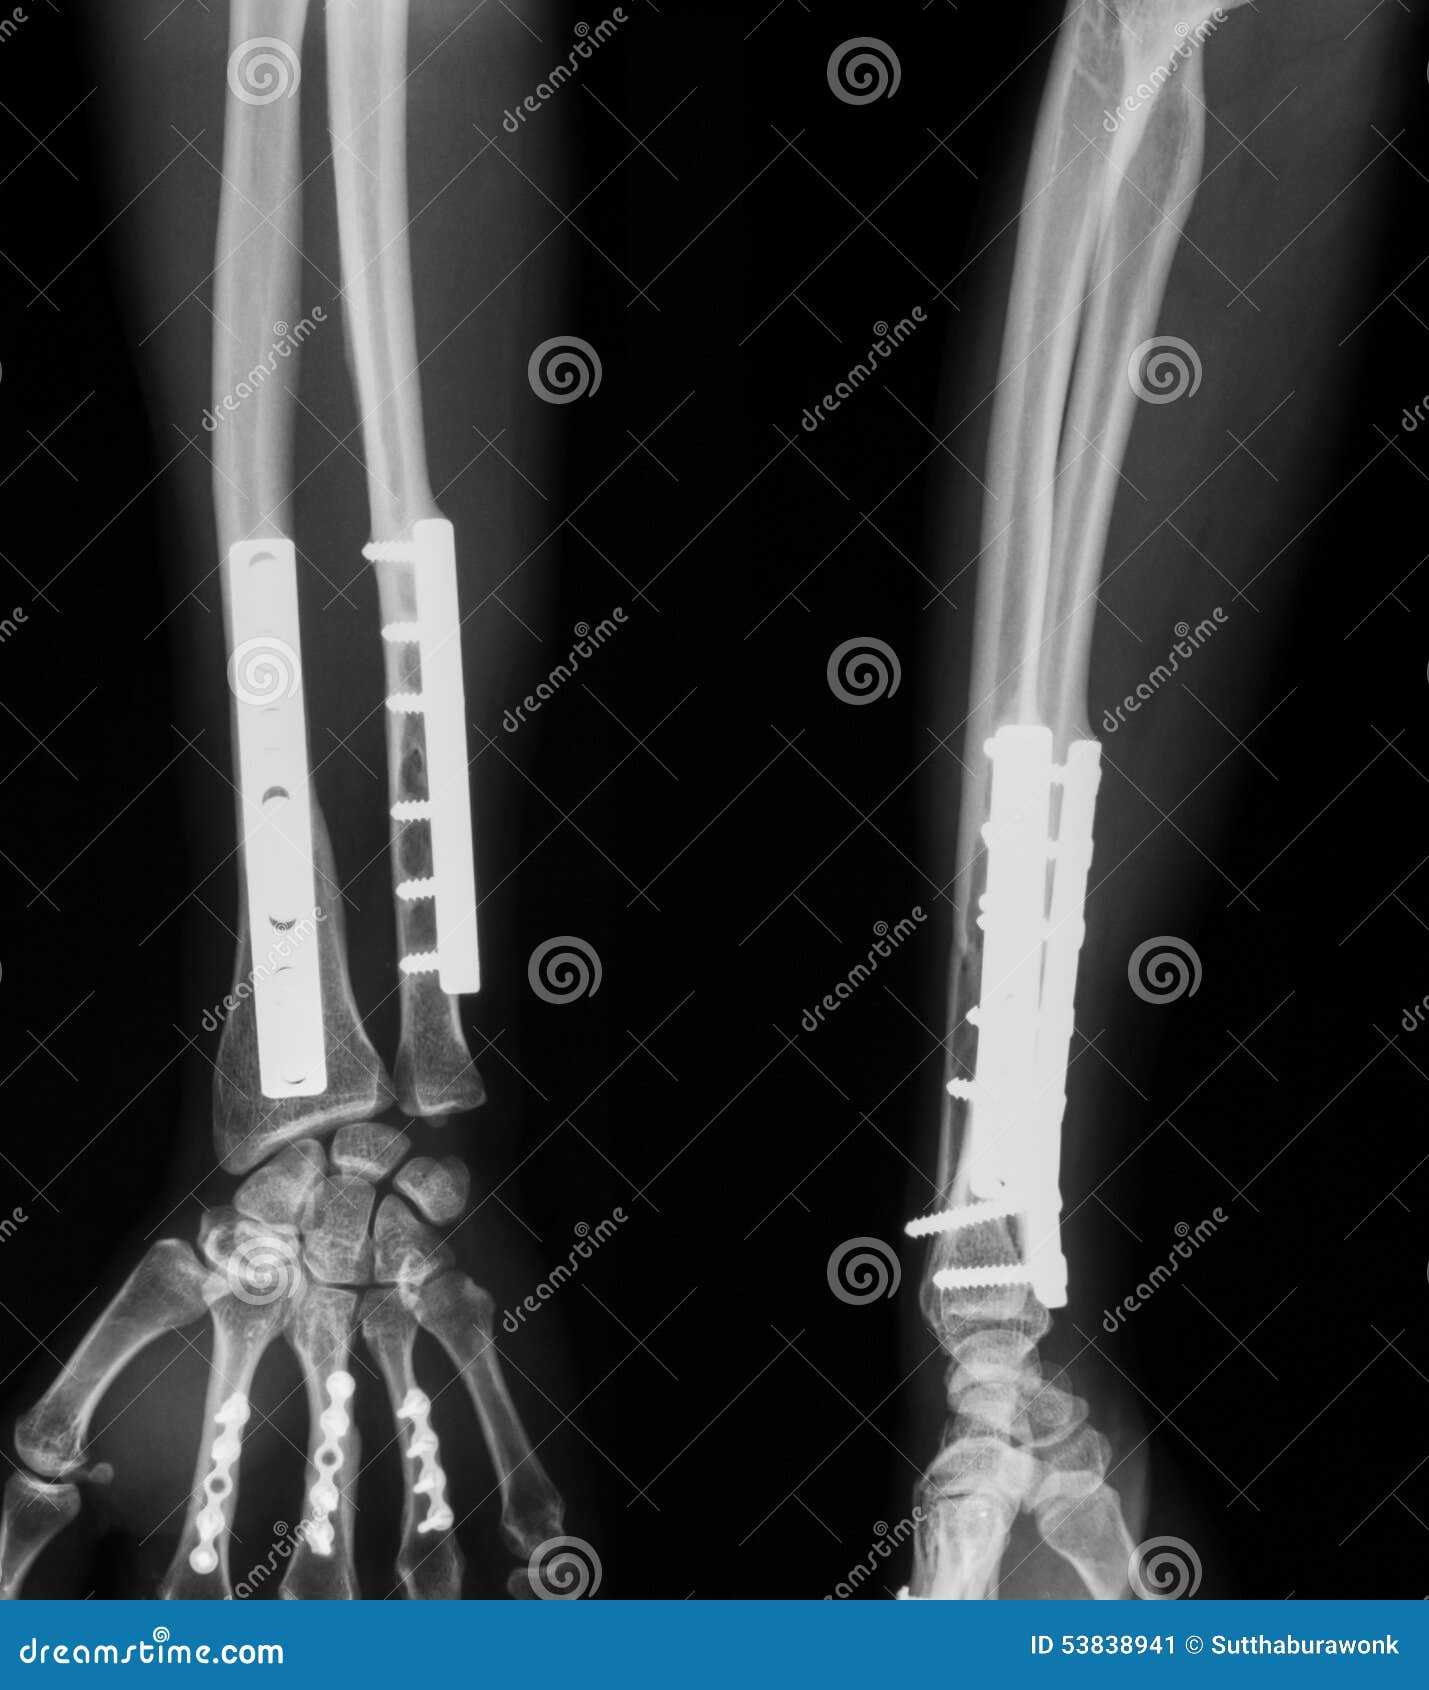

Premium Photo Fracture both bone of forearm. it was operated and

From www.dreamstime.com

Xray Image Of Broken Forearm. Stock Image Image 53838941 Metal Plate Broken Arm often, the metal plates and screws can stay inside your arm forever. bone fracture repair is a surgery to fix a broken bone using metal screws, pins, rods, or plates to hold the bone in place. However, if they bother you, they may need to be removed after the bones have healed. It’s more common to break one.. Metal Plate Broken Arm.